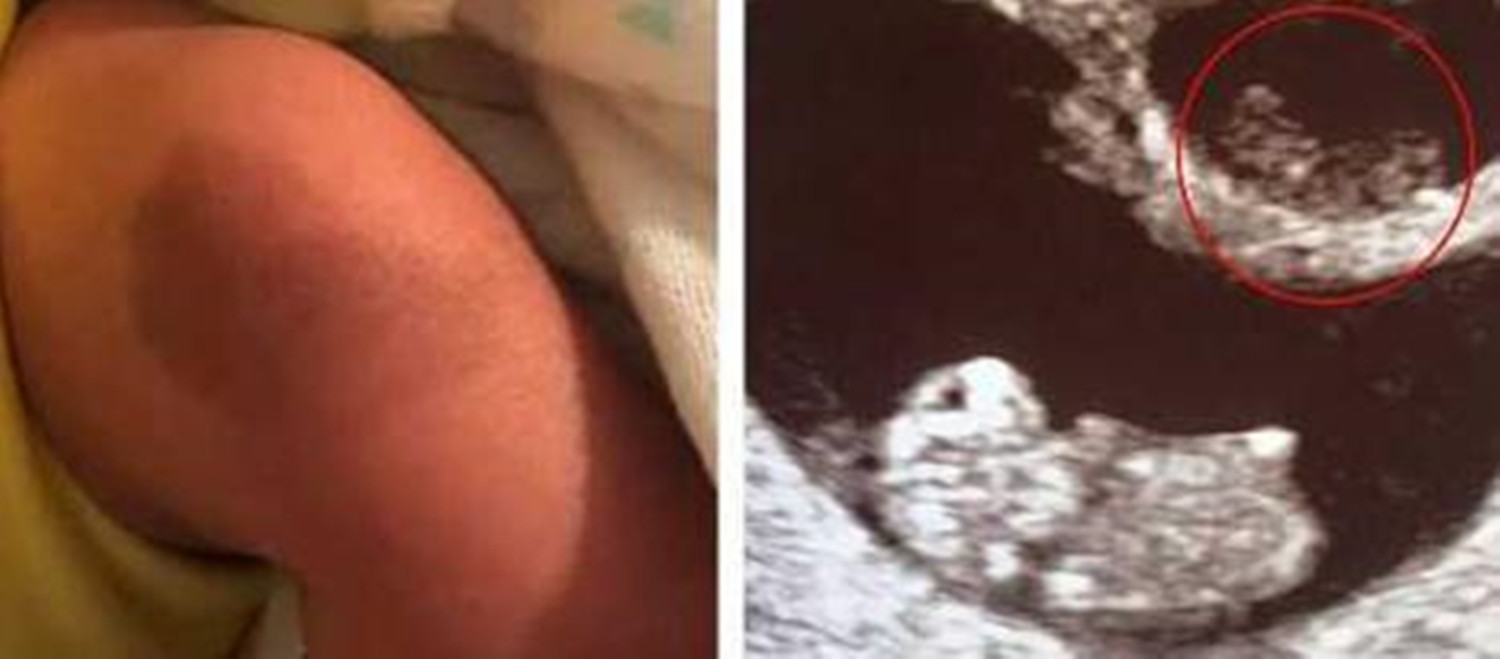

在怀孕的第13周,医生检查后说,超声图像显示腹部只有一个胎儿,另一个已经死亡并被吸收。听到这个消息,吉文斯伤心了好几天,并且还给这位未成年的妹妹命名,以示对他的纪念和深爱。幸运的是,最后,弟弟出生得很健康。使她感到惊讶的是,当护士把婴儿抱给她时,她还向她指出了腰果状的胎记,形状和“被吸收的”结节。B超检查的图像非常相似。Givens感到既惊讶又安慰,认为这可能是他未出生的妹妹留给弟弟的特殊回忆。他弟弟出生后腿上的胎记引起了很多关注。对于这一奇妙的巧合,网友评论道: